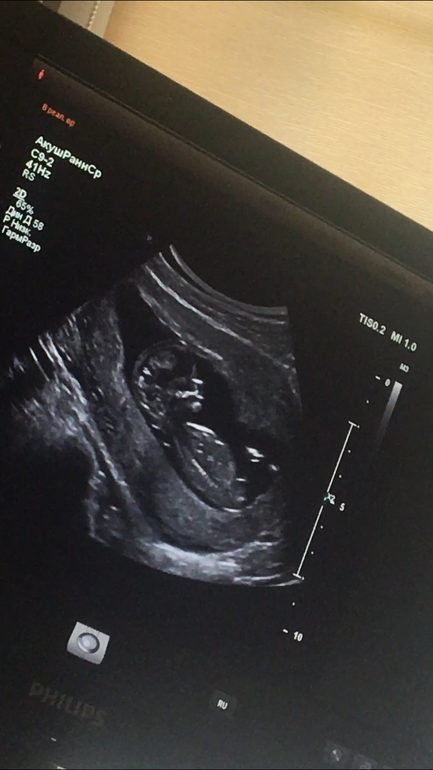

Наш первый скрининг 😍❤️ И пол крохи 😏

Результаты: УЗИ, КТГ, доплера, скринингаВот и прошли мы первый скрининг 😍 страха было..полные штаны 😂😂 но все просто идеально 😍🙏 врач раза три повторил что у меня и у ребёнка все хорошо 😂😂как будто понимал,что мне не верится 😂

теперь вопросик к вам девчонки,кто шарит в УЗИ и может распознать пол 😏 врач конечно же сам заговорил на эту тему,потому что не смотря на маленький срок он почти со стапроцентной уверенностью сказал пол 🙈 но я хочу у вас поинтересоваться))правда на столько видно?и кто же в теремочке живёт?😍